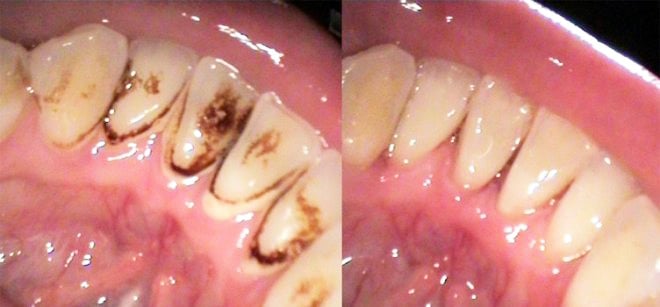

Diş taşı nedir?

Uzun süredir dişte bulunan plağın sertleşmesiyle oluşan yapıdır. Rengi sarı veya kahve rengi olabilir. Diş taşı oluşumu tükrük yapınıza, yaşa, ağız bakımınıza ve beslenme şeklinize göre değişkenlik gösterir.

Diş taşı pürüzlü yapısı nedeniyle daha çok plak birikimine sebep olur.